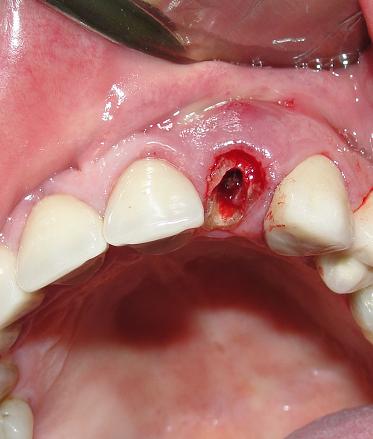

Extração da Raiz fraturada

Provisório logo após a extração